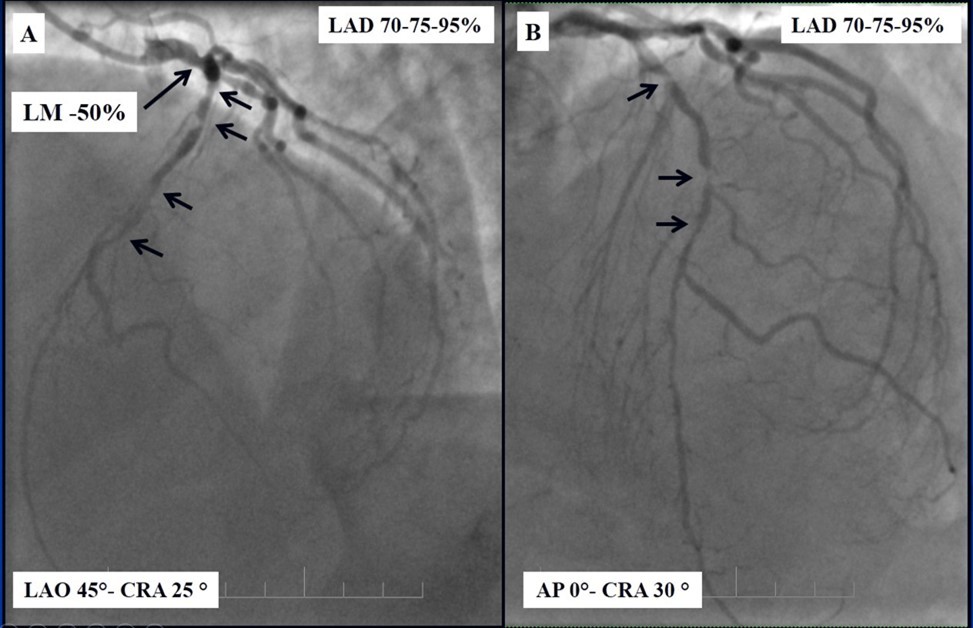

Angiography revealed rare anatomical variation LMCA quadrifurcation (Figure 1, Figure 2), 50% stenosis of the distal part of the LMCA, 40% stenosis of the ostial segment of left anterior descending (LAD) artery and diffuse prolonged 70-75-95% stenosis in mid-segment (Figure 3), 75% stenosis of the ostial segment of the circumflex (CX) artery, 75% stenosis of the ostial segment of the first marginal branch (OM1), 75-90% stenosis of the proximal segment of the intermediate artery (IMA), prolonged diffuse severe 90-95% stenosis of mid-segment of the right coronary artery (RCA) (Figure 4).

Figure 4.A - 50% stenosis of the distal segment of the LMCA; B - 70-75-95% stenosis in mid-segment of the LAD.